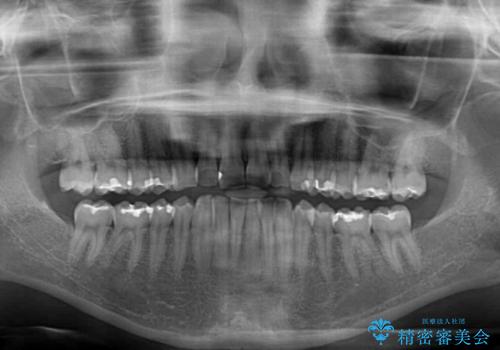

- 上下前歯の重なりを気にして来院された患者様です。

安価なインビザラインパッケージを用いての治療を希望されており、デコボコの程度が中等度であったため、インビザライン・モデレートを用いて矯正治療を行うこととしました。